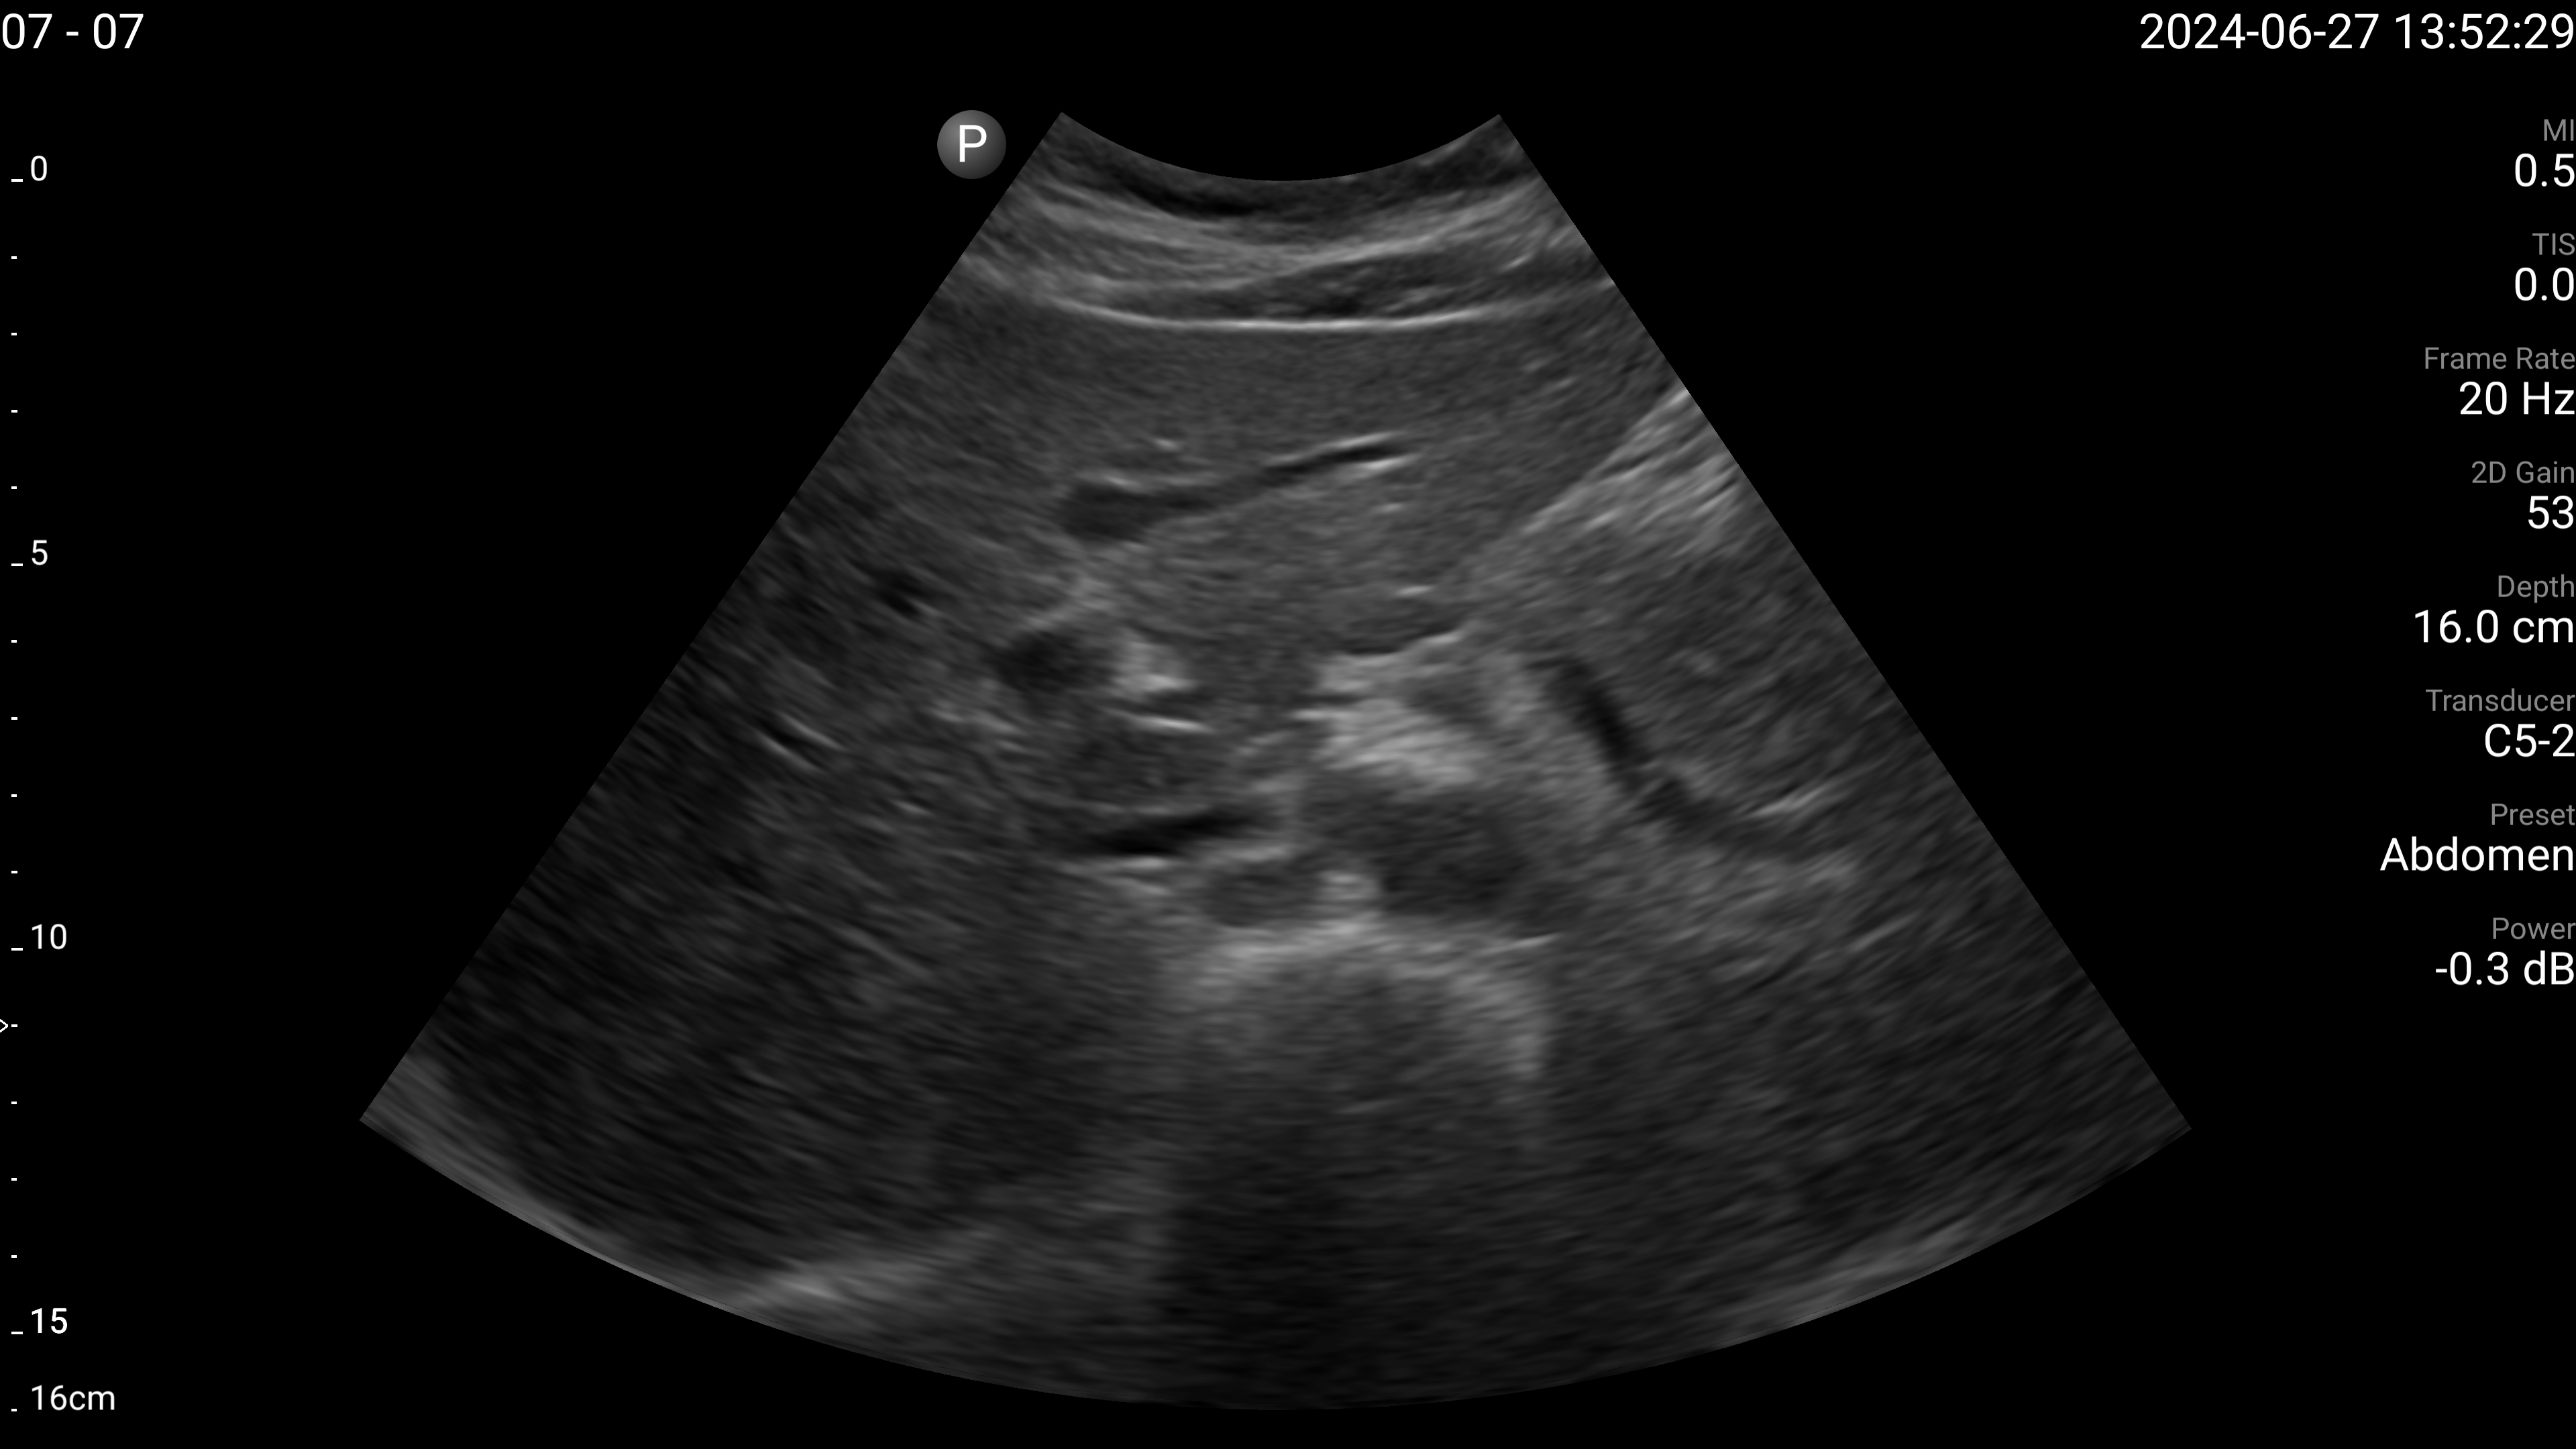

Refer to caption

(a) Proximal aorta with AP diameter.

(b) IVC - longitudinal.

(c) Left lobe of liver - long axis.

(d) Left lobe of liver - transverse.

(e) Right portal vein - transverse.

Figure 4: Examples of the target US images acquired by the sonographers using the human teleoperation system.

The sonographers completed 11 abdominal US scans, each with 5 target images and measurements for a total of 55 images. An example image of each of the targets acquired during these tests is shown in Fig. 4. After completing the scans, two radiologists scored the images based on quality, including identifying targets that could not be seen or were not captured (which were given a score of 0). The distribution of these scores is illustrated in Fig. 5. The first radiologist identified 4 out of the 55 targets as not visible, while the second radiologist identified 6 out of 55 as not visible. Combined, this accounted for 7 unique targets that at least one radiologist considered missing. Of these missing targets, three were not captured due to large amounts of bowel gas and body habitus while one was seen but the sonographer did not capture and save the image. When excluding all the missing targets, the images obtained a mean score of 4.28±0.95plus-or-minus4.280.954.28\pm 0.954.28 ± 0.95 out of 5 and 91.7% of the images were scored 3 or higher by both radiologists. A score of 3 or higher indicated the image quality was sufficient for basic image interpretation. 31.3% of the images were scored 5 by both radiologists, indicating the image quality was good and meaningful image interpretation was easy.